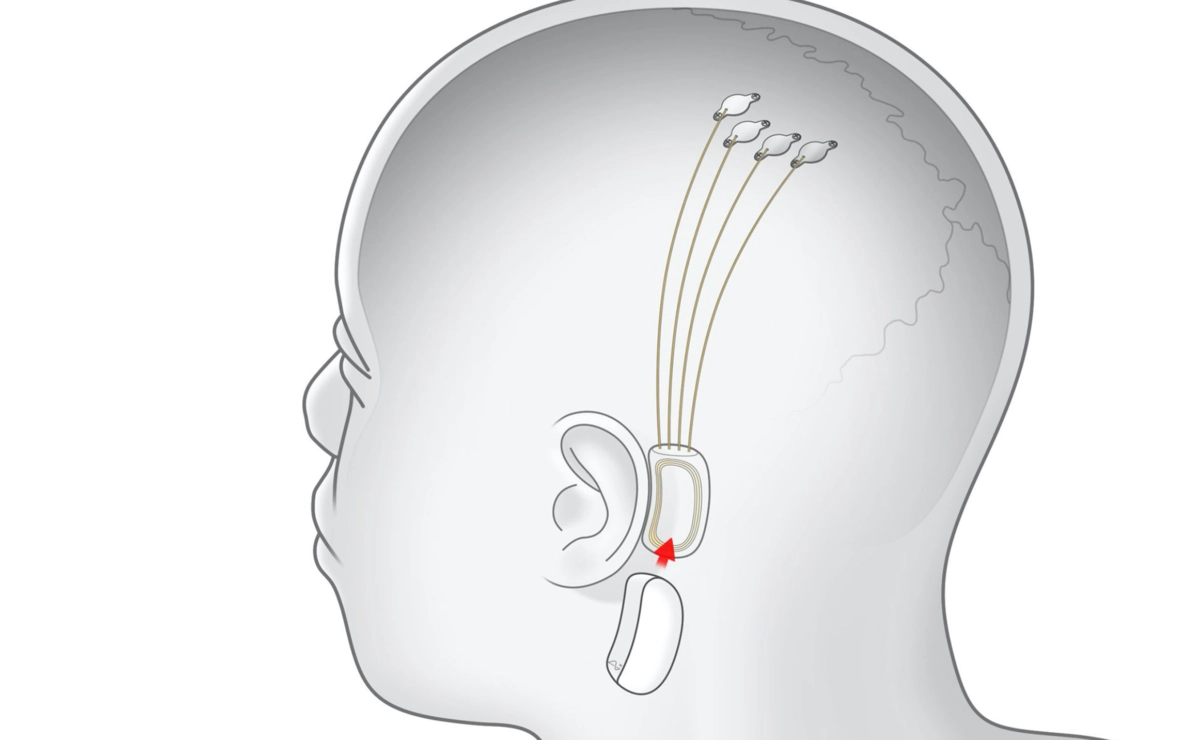

Проект Илона Маска Neuralink показал технологию, позволяющую вживлять электронные чипы в мозг. Подобные импланты будут применяться в медицинских целях — они помогут парализованным людям использовать смартфоны и компьютеры.

Основой технологии стали специальные «нити» толщиной 4−6 мкм, вживляемые в мозг при помощи сверлящих игл. По ним чип считывает электрическую активность мозга, делая это в десять раз быстрее современных нейроинтерфейсов.

Вживление чипа осуществляется при помощи специального робота, который за минуту устанавливает до 6 «нитей» со 192 электродами. При этом он избегает повреждения кровеносных сосудов и снижает вероятность отторжения.

Данные считываются микропроцессором, который подключается к компьютеру по USB-C. Сейчас инженеры работают над беспроводной версией чипа, которой можно управлять со смартфона.